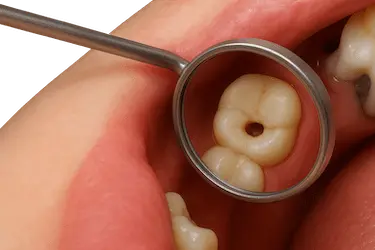

Las caries que avanzan hasta el interior del diente pueden llegar al nervio y causar una infección severa.

Con la endodoncia se elimina la pulpa dañada y se evita la extracción del diente.

El tratamiento de endodoncia es necesario cuando la cavidad o hueco del diente es muy profunda y llega al nervio.